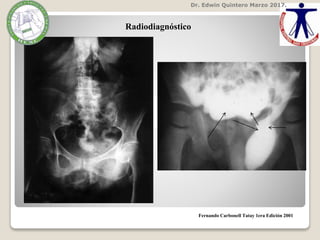

Radiodiagnóstico

Dr. Edwin QuinteroMarzo 2017. Fernando Carbonell Tatay 1era Edición 2001 Radiodiagnóstico